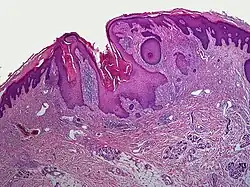

A dilated pore, also known as a dilated pore of Winer, is a cutaneous condition characterized by a solitary, prominent, open comedo on the face or upper trunk of an individual.[1]: 675 Louis H. Winer is credited with discovering the dilated pore. [2][3]